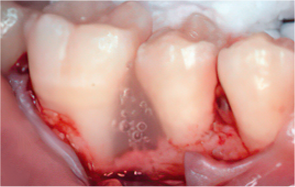

STEP 04

엠도게인 도포

-

STEP 05

클렌징

STEP 06

판막을 봉합